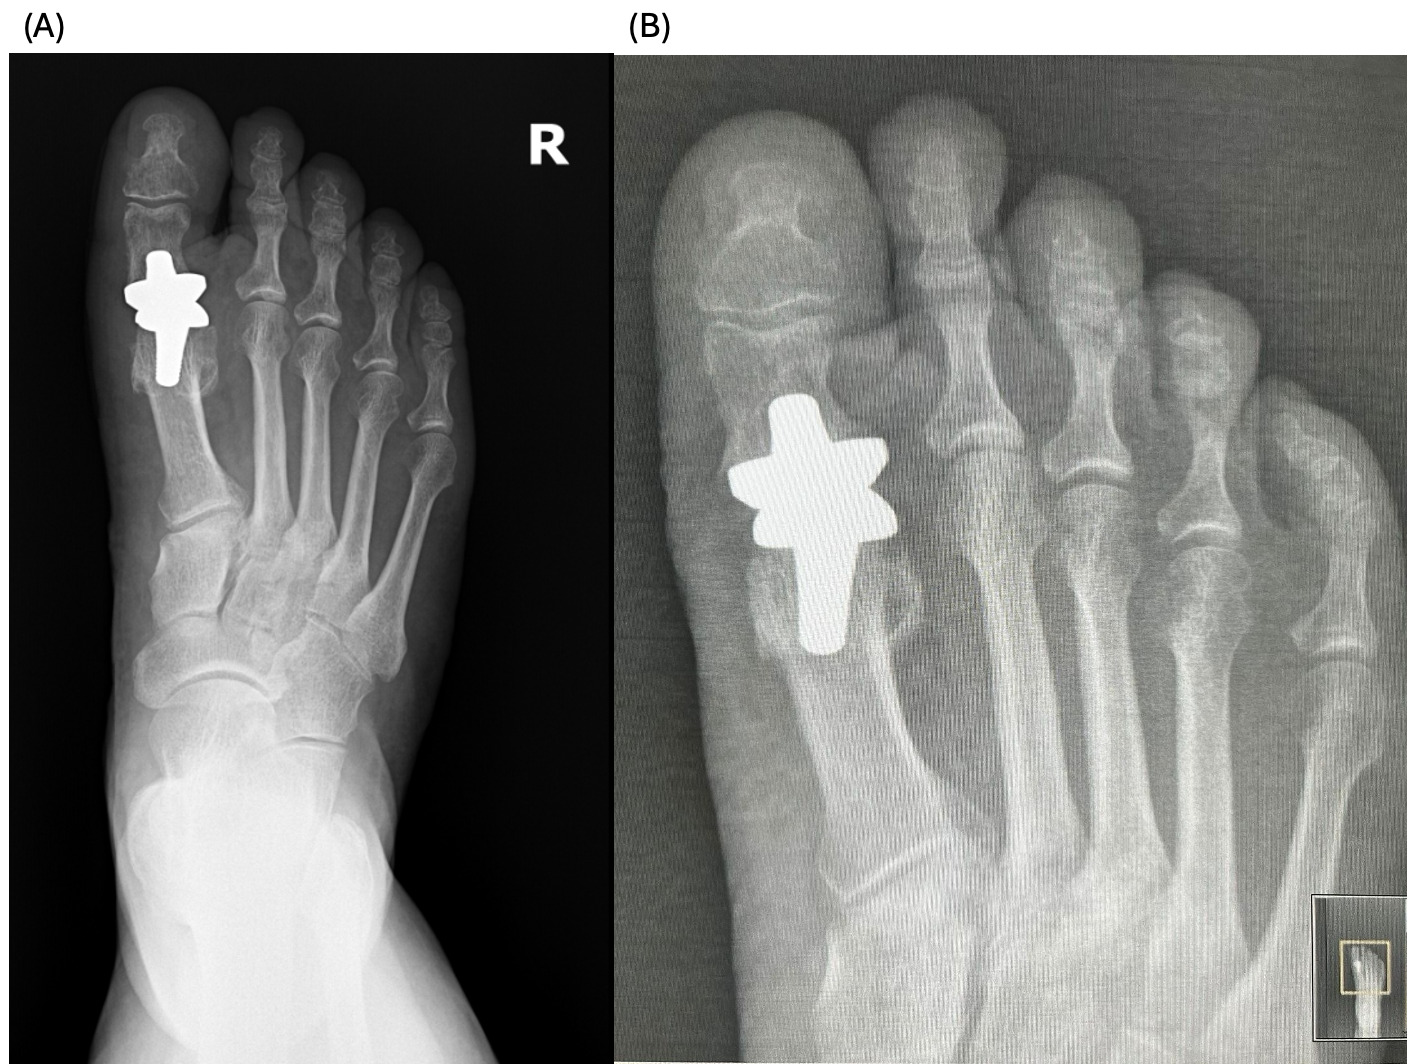

The patients had undergone radiographic evaluation of the MTP joint before the surgery, right after surgery, and 2 and 6 months after surgery (Figures 4-9). The radiographic imaging after the surgery confirmed the correct positioning and alignment. At the follow-up, the radiographic images were done to analyze the early healing process, to observe if there were any signs of implant loosening. 2 months after the surgery, no patient had periprosthetic radiolucencies, no stress-related changes. 6 months after surgery, no osteolysis, no migration of the implant.

This case series demonstrates successful short-term results following total first metatarsophalangeal (MTP) joint replacement using ceramic implants in patients with hallux rigidus. All three patients presented significant improvement in AOFAS scores within 2 months postoperatively, with preserved improvement at 6 months. Notably, Patient C, who had the lowest preoperative score (27/100), achieved the greatest relative improvement, reaching 92/100 at 2 months and 89/100 at 6 months. These functional outcomes were confirmed by physical examination findings, with clear improvements in joint alignment and reduction in deformity (Figure 1-3, (B, C)). Moreover, radiographic imaging revealed no signs of complications such as implant loosening, migration or stress-related changes.

._patient_c__immediate_postoperative_radiograph_(b).png)

._patient_c__6-month_follow-up_radiograph_(b).png)